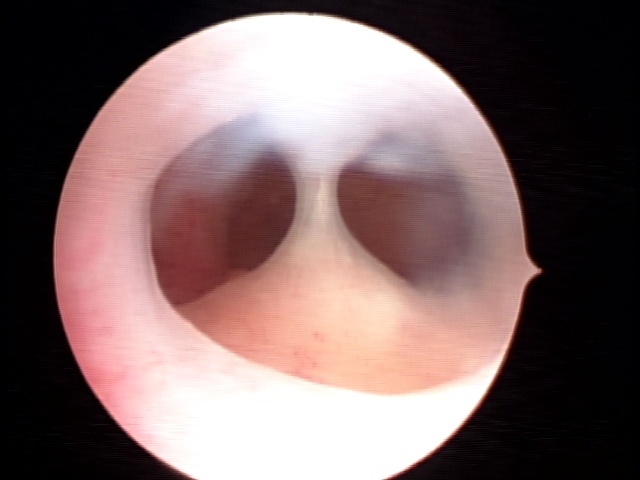

Durante o procedimento, a paciente permanece em posição ginecológica enquanto o ressectoscopio passa pela via vaginal e do colo do útero até o interior da cavidade uterina - sem incisões. Este aparelho contém uma lente óptica capaz de aumentar em até 20x a imagem - transmitida em tempo real para um monitor de vídeo - além de uma alça metálica que, através da função de corte e coagulação, possibilita a retirada da patologia a ser tratada.

O útero septado é uma má-formação uterina congênita na qual o útero encontra-se divido em dois por um tecido fibroso - o septo uterino. Apesar de não apresentar sinais ou sintomas prévios, os septos completos e incompletos estão relacionados a abortamentos tardios, partos prematuros e infertilidade.

O diagnóstico é determinado a partir da ultrassonografia 3D ou da ressonância magnética. A vídeo-histeroscopia diagnóstica pré-operatória pode auxiliar na programação cirúrgica.